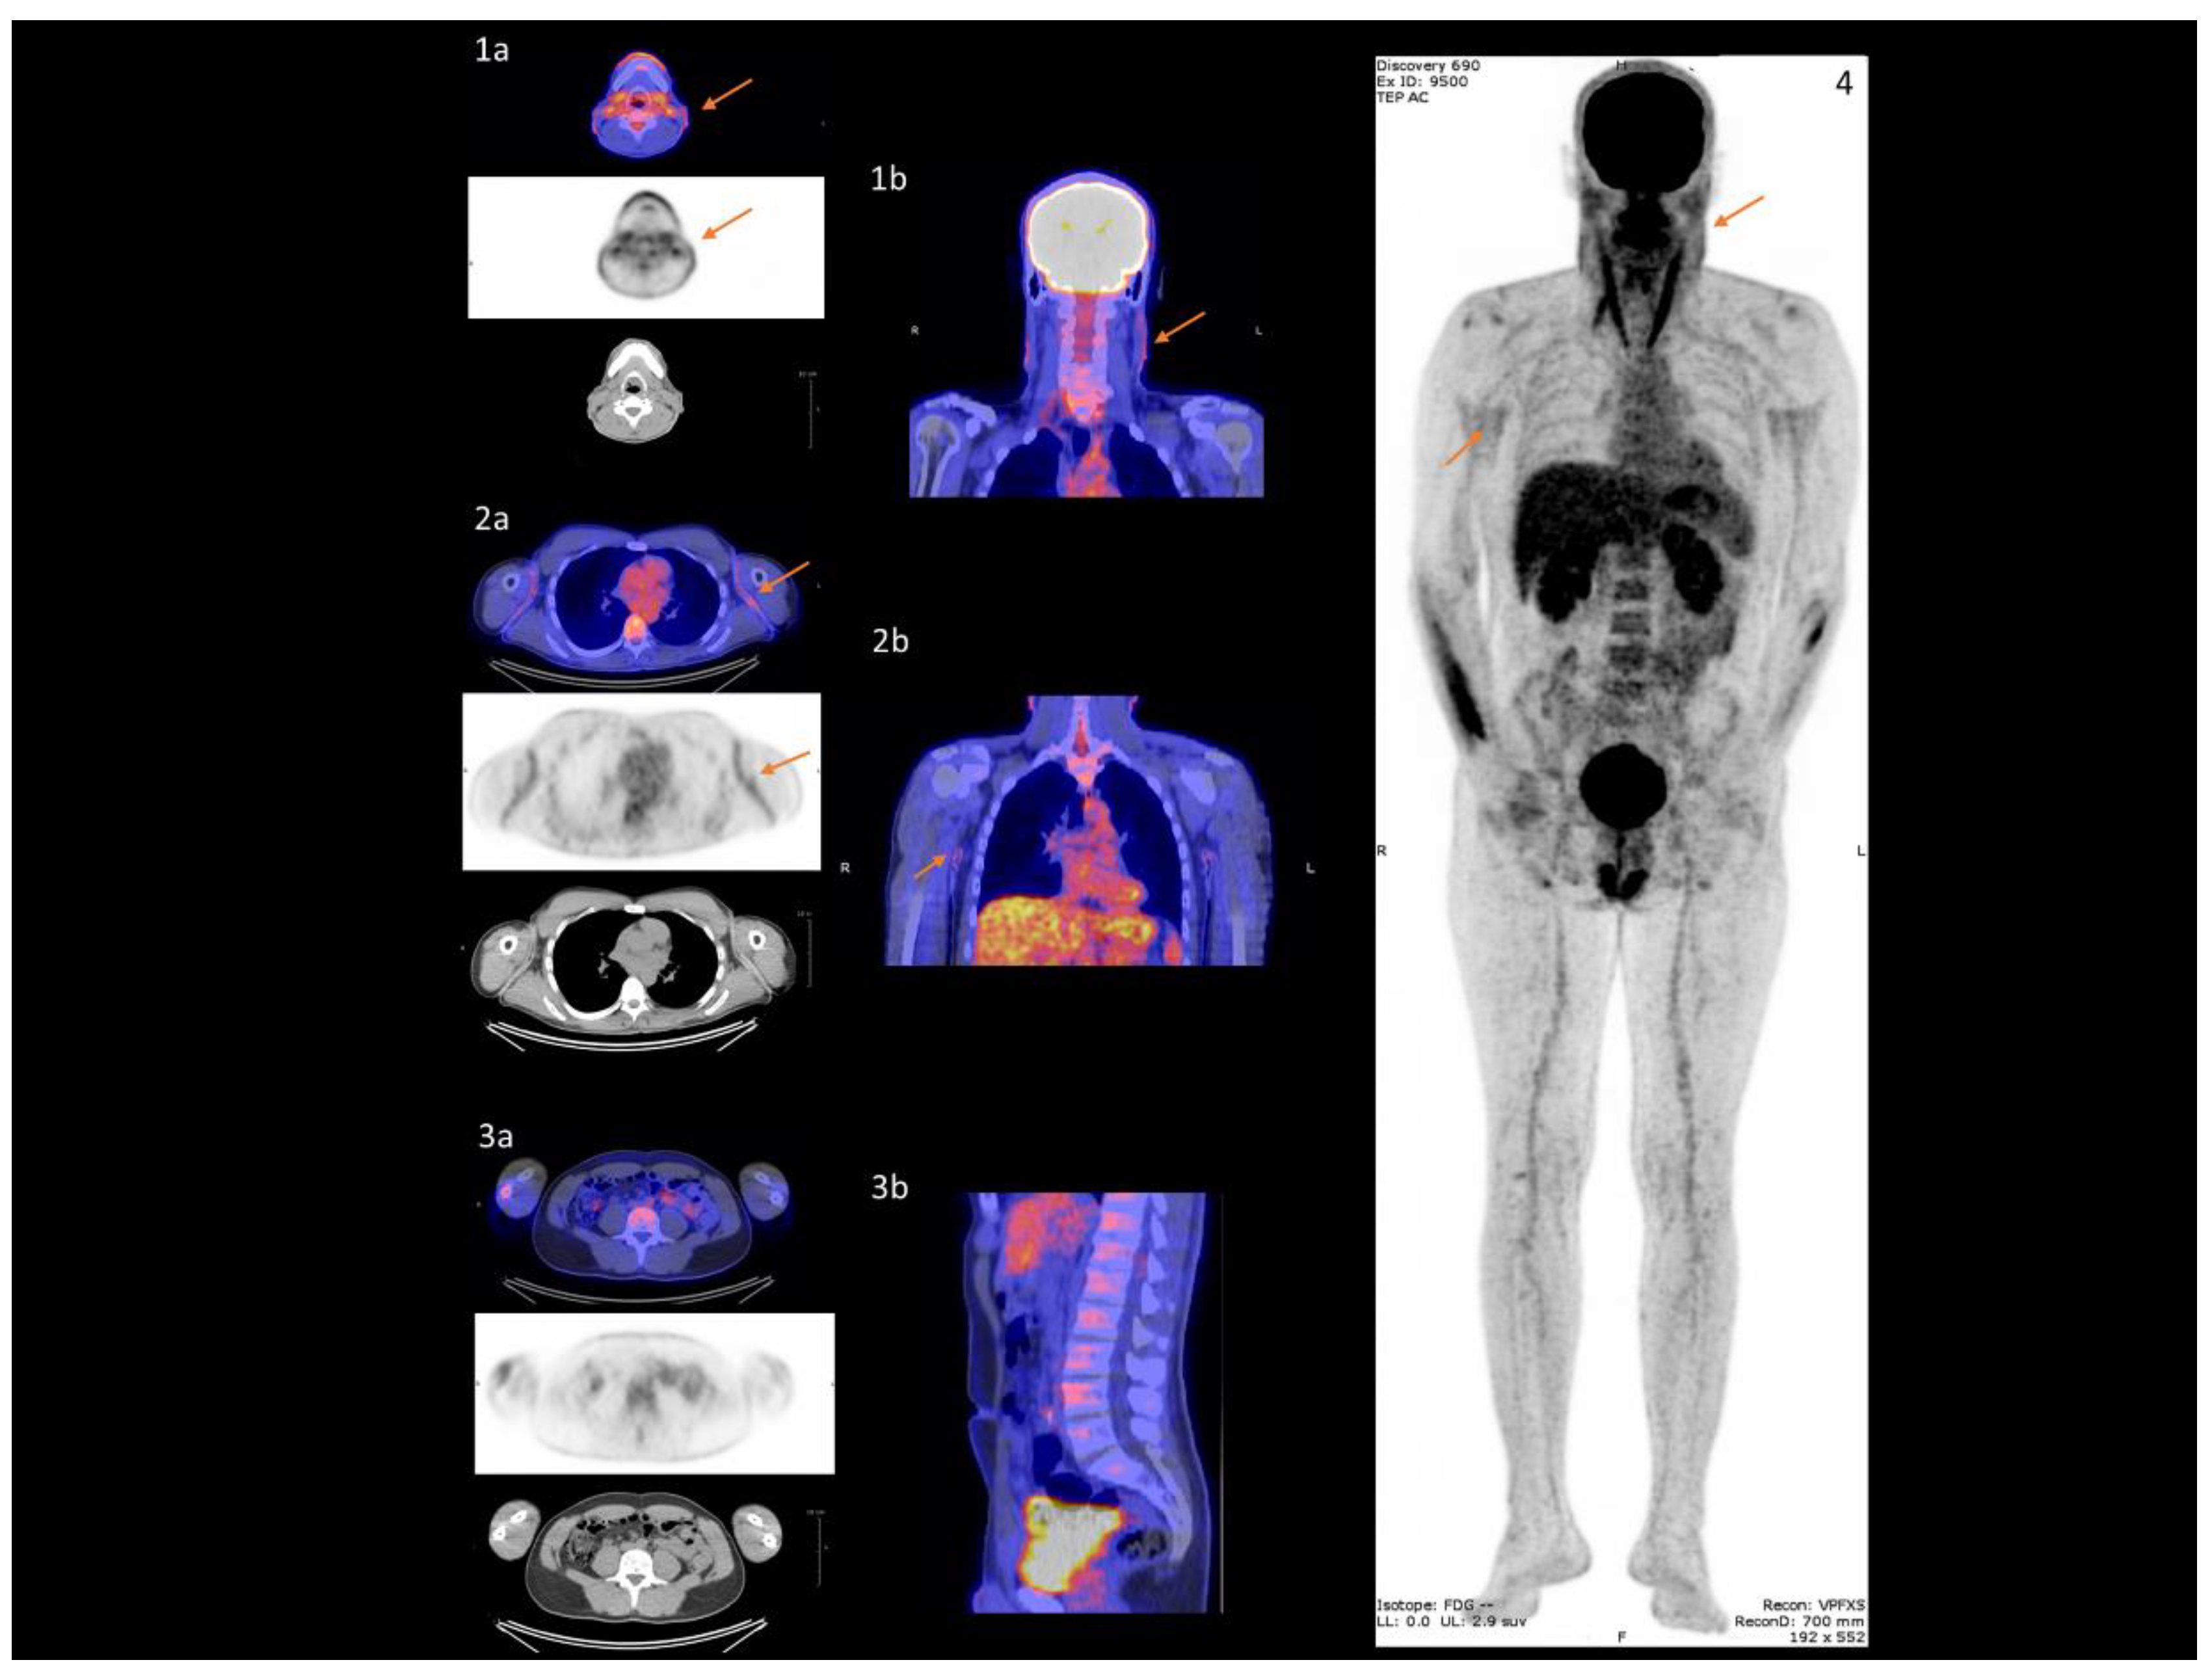

Each image dataset was analyzed by a nuclear medicine physician on an Imagys® workstation (Keosys®, Saint-Herblain, France). Maximum intensity projection PET-CT images were assessed visually for evidence of radiotracer accumulation in the femoral or popliteal artery walls, as previously described [18]. In semi-quantitative analysis, maximum SUV was determined by manually drawing an individual ROI 1 cm3 around the most fixed arterial segment (Figure 1) that included: the left and right carotid arteries, aorta (ascending aorta, aortic arch, descending aorta, abdominal aorta), left and right iliac arteries, damaged left and right femoral arteries and spared left and right popliteal arteries, as shown on coregistered transaxial PET-CT findings. The ROI was adjusted to the vascular wall using coronal and sagittal PET-CT images. Blood pool SUVmax/mean was expressed as the SUVmax/mean of a 1 cm fixed diameter ROI drawn mid lumen in the superior and inferior vena cava, as previously described [19]. The SUVmax of each artery lesion was divided by blood pool SUVmax to ascertain TBRmax [13,20]. For the purposes of analysis, mean TBR in the left and right carotid, iliac, femoral, popliteal arteries and the proximal (ascending aorta and aortic arch) and distal aorta (descending and abdominal aorta) was calculated [18] (Figure 1). TBR in the left and right carotids and the proximal aorta was calculated by dividing the SUVmax by SUVmax derived from the superior vena cava [21]. TBR in the distal aorta, iliac, femoral and popliteal arteries was calculated by dividing the SUVmax by SUVmax derived from the inferior vena cava [21]. With respect to skin analysis, SUVmax and SUVmean were measured after a circular ROI had been drawn around three regions (spared lumbar/damaged neck/axillary folds) [22]. Mean linear SUV was calculated in the left and right axillary folds [22].

Figure 1.

Whole-body 18F-FDG/18F-NaF-PET/CT to assess subclinical arterial inflammation and active mineral deposition. Skin/arterial inflammation quantified as 18F-FDG SUVmax. Active mineral deposition quantified as 18F-NaF SUVmax. SUVmax was determined by manually drawing an individual ROI 1cm3 around the most fixed arterial segment. TBRmax in vascular system obtained by dividing artery SUVmax by vena cava (blood pool) SUVmax. SUVmax measured from ascending to abdominal aorta as mean total aorta (meanTBR) in addition to neck, axillary fold and lumbar skin regions.

In all 23 PXE patients, skin imaging revealed significantly higher 18F-FDG uptake in the neck (Figure 2(1a,1b)) and axillary folds (Figure 2(2a,2b)) than in normal lumbar skin (Figure 2(3a,3b)) (neck SUV = 1.30 (1.20;1.90) or axillary folds SUV = 1.80 (1.60;1.90) versus lumbar SUV = 0.90 (0.80;1.10); p < 0.0001), (Table 2). On vascular imaging, no difference in 18F-FDG uptake was found between the carotid, distal aorta, iliac, and popliteal artery wall. By contrast, there was evidence of significantly higher 18F-FDG uptake in the proximal aorta and femoral than in the popliteal artery wall (proximal aorta TBR = 1.32 (1.13;1.57) versus popliteal TBR = 0.91 (0.80;1.14); p < 0.0001), (femoral TBR = 0.89 (0.75;1.02) versus popliteal TBR = 0.91 (0.80;1.14); p = 0.03), (Table 2). No correlation was found between PWV and aorta wall 18F-FDG uptake (Supplementary Material, Figure S1a). Multivariate analysis established a significant link between BMI/HbA1c and aorta wall 18F-FDG uptake (p = 0.01 and p = 0.02 respectively).

Figure 2.

18F-FDG uptake in specific damaged skin in PXE. Damaged skin in neck (arrows (1a,1b)) and axillary folds (arrows (2a,2b)) vs healthy skin in lumbar region (3a,3b) on PET/CT imaging. Maximum intensity projection indicates damaged skin sites (arrow 4).